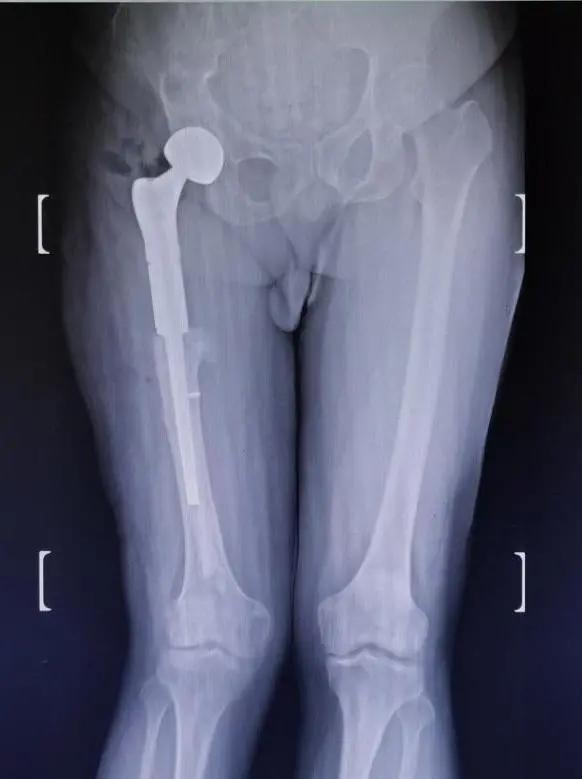

按照预定计划,患者一期进行了肩部的手术,手术及术后康复锻炼非常顺利。二期股骨手术,先把原来断裂的内固定物取出,再把畸形愈合的股骨近端从骨不连的地方切除,同时切除周围大量增生的骨痂,安装定制的人工股骨近端假体,并重建周围软组织平衡,历经2个小时的奋战,手术顺利完成。

先后两期手术都未予输血,不仅把几处骨折问题解决了,还把吴先生多年的老残一并给矫正了,通过植入的人工假体,左右腿长短已经相差无几,且没有之前担心的血管、神经损伤等并发症发生。术后在医护人员的细心呵护下,吴先生重新站立起来,告别了五十年跛行岁月,仍在康复中的他重新找回了自信,活出了精气神。